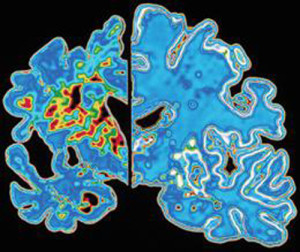

L’ESPERIMENTO. Nello studio, finanziato dal Medical Research Council e pubblicato su Nature, i ricercatori hanno osservato gli effetti del letargo sui due gruppi di topi, sani e con malattia di Alzheimer.Dopo 45 minuti di ipotermia a 16-18 gradi, al ripristino della temperatura fisiologica, la proteina è entrata in funzione nei soli topi sani e non nei malati, con conseguente mancato ripristino delle sinapsi al “risveglio”. Inoltre, la degenerazione dei neuroni tipica della malattia appare più accelerata tanto più basso il livello di RMB3.

L’IPOTERMIA CEREBRALE. L’abbassamento della temperatura corporea è utilizzato da tempo a scopo terapeutico sui pazienti con trauma cranico che vengono tenuti in coma e ipotermia proprio per mettere il cervello al riparo da ulteriori danni. Infatti, il trattamento dell’ipotermia cerebrale indotta in modo controllato, in altre parole il raffreddamento progressivo del paziente, permette di proteggere il cervello, rallentandone il metabolismo e quindi diminuendo la quantità di glucosio e di ossigeno consumato. Lo stato di torpore permette di risparmiare energia, dando tempo all’edema che segue il trauma cranico di riassorbirsi.